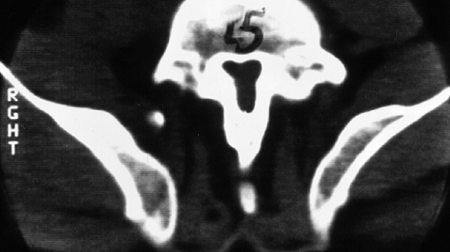

stenosis is explained by the fact that the spinal canal forms through

endochondral ossification at the neurocentral synchondroses (Fig. 8.4).

![]() |

|

Figure 8.4

This specimen radiograph shows the obliquely oriented neurocentral synchondroses that contribute, by endochondral ossification, to both dimensions of the spinal canal. Because this process is impaired in achondroplasia, stenosis results. |